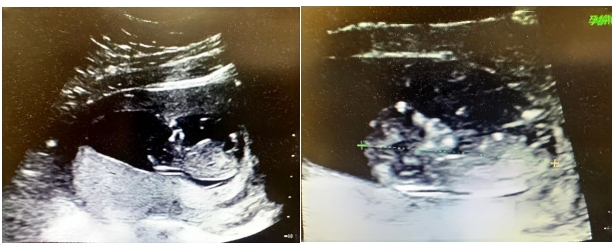

然而,命运似乎再次和吴女士开了一个玩笑,2024年10月第一次胚胎移植未孕。这对吴女士来说无疑又是一次沉重的打击,但乔主任没有放弃,她反复回顾病例、查阅相关文献,根据子宫内膜病变治疗史,为其精细调整移植方案。终于,在2024年11月第二次胚胎移植后,吴女士成功怀孕了!更令人惊喜的是,她怀上的还是双胞胎!这个消息让吴女士和她的家人喜极而泣,他们终于迎来了期盼已久的生命奇迹。目前吴女士已于生殖医学科顺利过渡至产科,为她孕期母婴健康保驾护航。